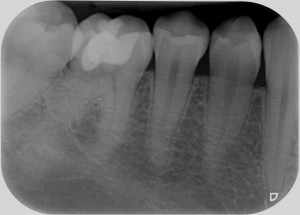

E tu credi che questo dente durerà meno di 3 anni? A meno che non ci sia un cataclisma in questi due mesi, ti posso già anticipare di no, perché a novembre questa cura compirà tre annetti e il dente è perfetto sia clinicamente che radiograficamente.

Riassorbimento esterno - Finale BongioanniRiassorbimento esterno - Radiografia finale Bongioanni